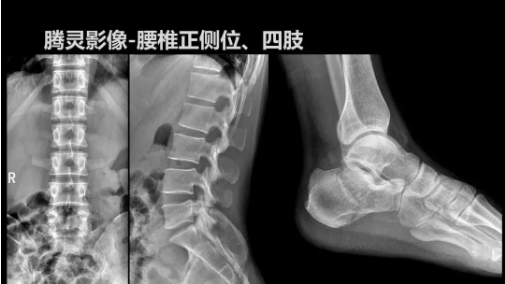

“騰靈”是安健科技的第四代動(dòng)態(tài)DR產(chǎn)品,可實(shí)現(xiàn)全科室應(yīng)用。如各類常規(guī)的X線檢查、消化道檢查、骨科檢查、婦科、兒科檢查等。此外,安健科技為“騰靈”在真正意義上實(shí)現(xiàn)多科室、多功能診斷進(jìn)行了多項(xiàng)針對(duì)性設(shè)計(jì)。

相較前代產(chǎn)品,“騰靈”在圖像質(zhì)量方面得到了全面升級(jí),“騰靈”采用17*17非晶硅平板探測(cè)器設(shè)計(jì),采集矩陣達(dá)3072*3072,動(dòng)態(tài)范圍達(dá)16bit,為成像提供超大視野的同時(shí)保證成像質(zhì)量,此外,該款機(jī)型可根據(jù)醫(yī)療機(jī)構(gòu)的差異化需求而選配不同的動(dòng)態(tài)平板探測(cè)器,以此來(lái)適應(yīng)不同階層用戶所需。

此外,“騰靈”為了能夠幫助醫(yī)生更快速、有效的定位病灶,還增加了多項(xiàng)精準(zhǔn)診斷保障功能,如支持動(dòng)態(tài)觀察診斷,實(shí)時(shí)高清點(diǎn)片等。“騰靈”透視切換高清點(diǎn)片曝光,捕捉關(guān)鍵病灶診斷僅需0.8s,同時(shí)還支持圖像局部放大,醫(yī)生可自由切換15’12’和9’三種放大模式,另外,“騰靈”還支持視頻保存、回放功能,幫助醫(yī)生在檢查結(jié)束后通過(guò)回放查看細(xì)節(jié),為醫(yī)生的診斷增加信心。